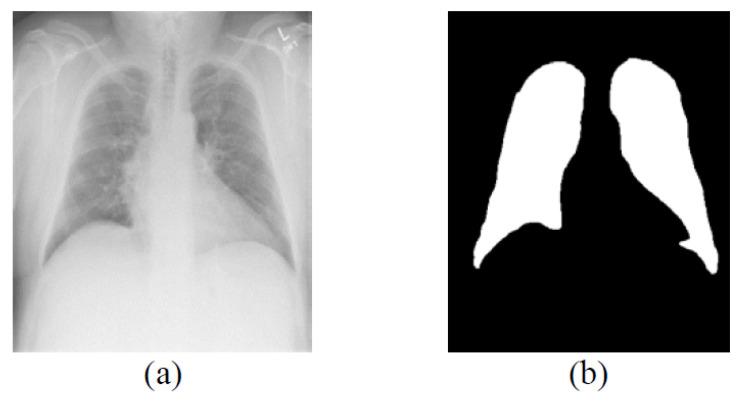

Lung segmentation of chest X-ray (CXR) images is a fundamental step in many diagnostic applications. Most lung field segmentation methods reduce the image size to speed up the subsequent processing time. Then, the low-resolution result is upsampled to the original high-resolution image. Nevertheless, the image boundaries become blurred after the downsampling and upsampling steps. It is necessary to alleviate blurred boundaries during downsampling and upsampling. In this paper, we incorporate the lung field segmentation with the superpixel resizing framework to achieve the goal. The superpixel resizing framework upsamples the segmentation results based on the superpixel boundary information obtained from the downsampling process. Using this method, not only can the computation time of high-resolution medical image segmentation be reduced, but also the quality of the segmentation results can be preserved. We evaluate the proposed method on JSRT, LIDC-IDRI, and ANH datasets. The experimental results show that the proposed superpixel resizing framework outperforms other traditional image resizing methods. Furthermore, combining the segmentation network and the superpixel resizing framework, the proposed method achieves better results with an average time score of 4.6 s on CPU and 0.02 s on GPU.

胸部X光(CXR)图像的肺部分割是许多诊断应用中的基本步骤。大多数肺野分割方法会缩小图像尺寸以加快后续处理时间。然后,将低分辨率结果上采样到原始高分辨率图像。然而,在降采样和上采样步骤之后,图像边界会变得模糊。有必要在降采样和上采样过程中减轻边界模糊。在本文中,我们将肺野分割与超像素缩放框架相结合以实现这一目标。超像素缩放框架基于从降采样过程中获得的超像素边界信息对上采样分割结果。使用这种方法,不仅可以减少高分辨率医学图像分割的计算时间,还可以保留分割结果的质量。我们在JSRT、LIDC-IDRI和ANH数据集上评估了所提出的方法。实验结果表明,所提出的超像素缩放框架优于其他传统图像缩放方法。此外,将分割网络与超像素缩放框架相结合,所提出的方法取得了更好的结果,在CPU上的平均时间得分是4.6秒,在GPU上是0.02秒。